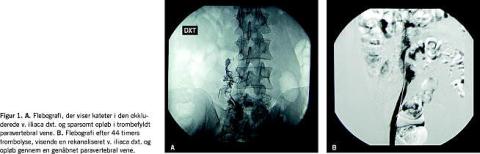

Der blev rejst mistanke om bilateral DVT, hvilket blev bekræftet af duplex-skanning og flebografi, der afslørede total trombosering af vv. popliteae, vv. femorales og vv. iliacae (Figur 1A). Der blev samtidig påvist agenesi af v. cava inferior til leverniveau, hvorfor det venøse afløb skete via delvist tromboserede veludviklede paravertebrale vener.

Der blev indledt katetervejledt lokal trombolyse med bilateral anlæggelse af sidehulskatetre i tromberne via vv. poplitea og infusion af lavdosis alteplase med 0,6 mg pr. time i hvert ben og dosisjusteret ufraktioneret heparin på ca. 1.500 IE pr. time. Afsluttende flebografikontrol efter 44 timers trombolyse viste næsten total tromberegression bilateralt med enkelte mindre randstillede tromber i venstre v. iliaca samt spontant afløb i de rekanaliserede paravertebrale vener (Figur 1B). Patienten blev udskrevet i velbefindende efter seks dage, han skulle fortsat behandles med høje graduerede kompressionsstrømper, selvadministreret tinzaparin i 14 dage og peroral antikoagulans (AK). Ved kontrol efter et år var patienten symptomfri og havde åbent og sufficient dybt venesystem i begge underekstremiteter, hvilket blev visualiseret ved en ultralydduplexskanning. Ved fortsat AK-behandling forventes det, at patienten kan fortsætte med at være symptomfri og undgå posttrombotisk syndrom (PTS), da der foreløbig er konstateret normal veneklapsfunktion i begge ben.